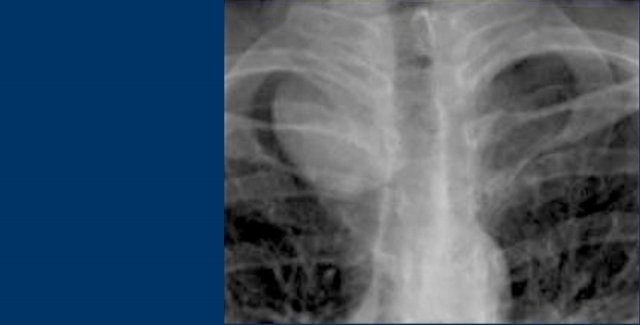

On the left you see two different patients.

Describe the findings and continue.

On the x-ray on the left there is a lesion that has an acute border with the mediastinum.

This must be a lung mass.

The chest radiograph on the right shows a lesion with an obtuse angle to the mediastinum.

This must be a mediastinal mass.

Since there is a silhouette-sign with the right heart border - which is located anteriorly - we can deduce that the mass must be located within the anterior mediastinum.

The lesion on the left was a pancoast tumor.

The lesion on the right was a thymoma, located within the anterior mediastinum.